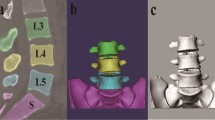

Ten asymptomatic subjects (M/F: 5/5; age: 40–60 years) were recruited. The lumbar segment of each subject was MRI-scanned to construct 3D models of the L2–S1 vertebrae. The lumbar spine was then imaged using a dual fluoroscopic imaging system as the subject performed a weight-lifting activity from a lumbar flexion position (45°) to maximal extension position. The 3D vertebral models and the fluoroscopic images were used to reproduce the in vivo vertebral positions along the motion path. The relative translations and rotations of each motion segment were analyzed.

Experiment setup

A validation study was performed to evaluate the accuracy of the DFIS technique when used to determine human lumbar spine kinematics during dynamic motion. In this validation, a cadaveric human body segment from feet to chest was acquired. The body segment included the entire lumbar spine and had all the surrounding soft tissues intact. Titanium beads (MRI compatible) of 4 mm in diameter were implanted into the L3, L4 and L5 vertebrae by a spine surgeon (Fig. 5). The lumbar spine was then MRI-scanned using the protocol described in the Sect. “Materials and methods”. The contours of L3, L4, L5 vertebrae and the beads were digitized from the MR images to reconstruct their 3D mesh models. A local coordinate system was created for each spine vertebral segment model as described in our previous study [35]. The specimen was then placed in a sitting position and the lumbar spine was manually flexed to simulate a dynamic physiologic flexion–extension motion at a rotation speed of ~50°/second. The test was guided using a timer. Dynamic orthogonal images of the lumbar spine were taken simultaneously from the anteromedial and anterolateral directions using two fluoroscopes (Fig. 2a).

The spatial positions of the vertebral bodies during the flexion–extension motion were reproduced in Rhinoceros® software through 3D to 2D imaging matching (Fig. 6), as described in the Sect. “Materials and Method”. To evaluate the accuracy of the image matching technique of DFIS in reproducing vertebral motion, five positions were chosen along the dynamic motion path of the spine: maximum flexion, middle flexion, upright, middle extension and maximum extension. Each position was independently reproduced using both the vertebral body matching technique (DFIS method) and the beads position matching technique (RSA method––gold standard) [35]. The positions and orientations of each vertebra determined using the DFIS and RSA methods were compared to evaluate the accuracy of the DFIS method in determination of dynamic lumbar kinematics.